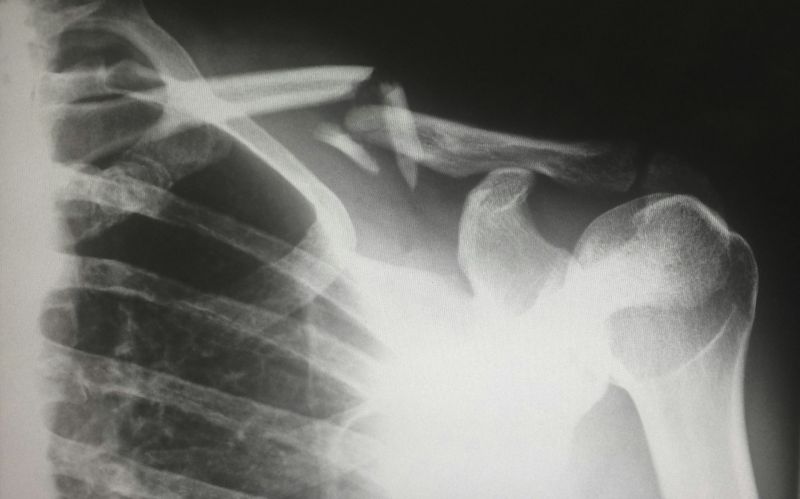

Magnetna rezonanca ramena i česte promene nakon 40. godine

Magnetna rezonanca ramena pokazuje da su promene na rotatornoj manžetni izuzetno česte kod osoba starijih od 40 godina, bez obzira na to da li postoji bol. U velikoj populacionoj studiji sprovedenoj u Finskoj, uz učešće stručnjaka iz drugih zemalja, analizirano je više od 600 odraslih osoba uzrasta od 41 do 76 godina.

Detaljna analiza pokazala je da su promene prisutne kod 98,7% ispitanika. Među njima su najčešće:

• promene na tetivama (tendinopatija) kod oko četvrtine ispitanika

• delimična oštećenja tetiva kod više od polovine

• potpuna oštećenja tetiva kod manjeg broja osoba

U više od 1200 analiziranih ramena, promene su uočene kod 96% onih bez tegoba i 98% kod osoba koje imaju bol.